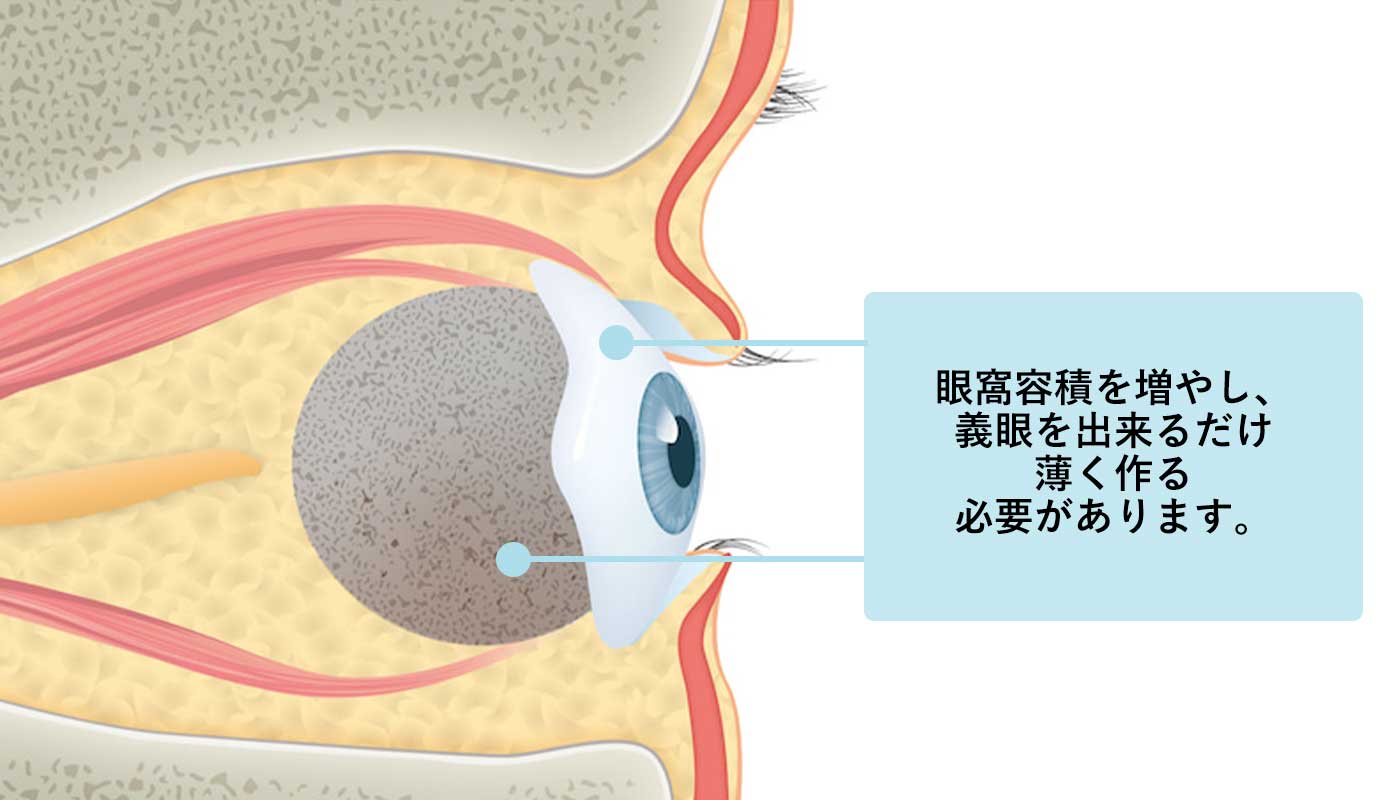

では、下まぶたがこのような状態になってしまうとすれば、どう対処すれば良いのか。

それは眼窩容積を増やし、義眼を出来るだけ薄く作るということが答えになります。

義眼を出来るだけ薄く作ることで、下まぶたへの圧力を減らすことが出来ます。

でもそうするともちろん上まぶたのへこみはより悪化してしまいます。

そのために必要なのが、そもそもの眼窩容積を増やすこと。

眼球が小さくなったり、無くなったりした分の容積を補う必要があります。

眼窩容積を増やすためには、何かを眼窩に入れる必要があります。